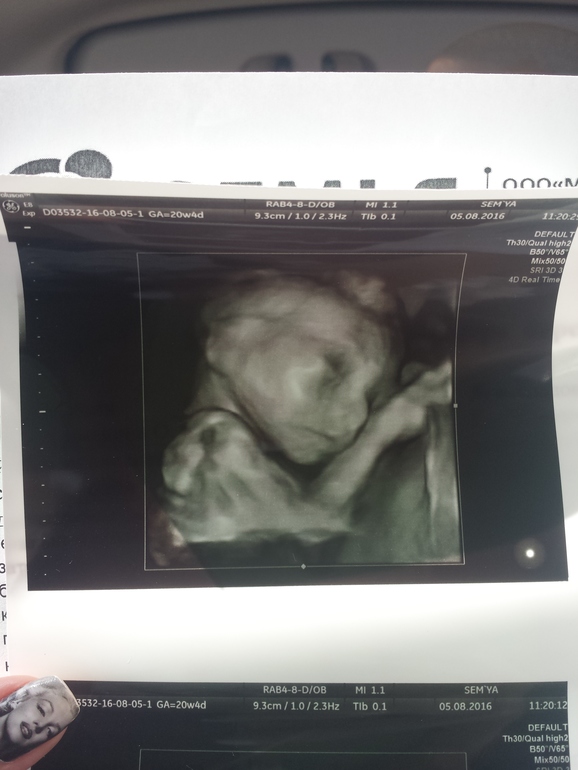

Ну вот мы и прошли уже второй скрининг)все у нас хорошо,все в норме)весим 340 гр,чсс 144.плацента по передней стенке,по центру.кол-во околоплодных вод нормальное.пуповина имеет 3 сосуда,степень зрелости 0.длина шейки матки 35(на 5 мм укоротилась,сказали не страшно,но мониторить раз в месяц).лежим головкой вниз и точно по сроку,не опережаем и не отстаем.и у нас будет доченька)))муж наверное расстроился,хоть и вида не подает и говорит,что рад.но чувствую,что хотел больше сына и от этого мне немного не по себе(сама до последнего думала,что будет мальчик.но самое главное,что малышка здорова!слава Богу!!!единственное,что меня смутило-это кости носа 6.7.что носатенькая будет???вроде не в кого...долго не хотела показывать нам личико,отвернулась и закрывалась ручкой,но потом все же повернулась в профиль)))